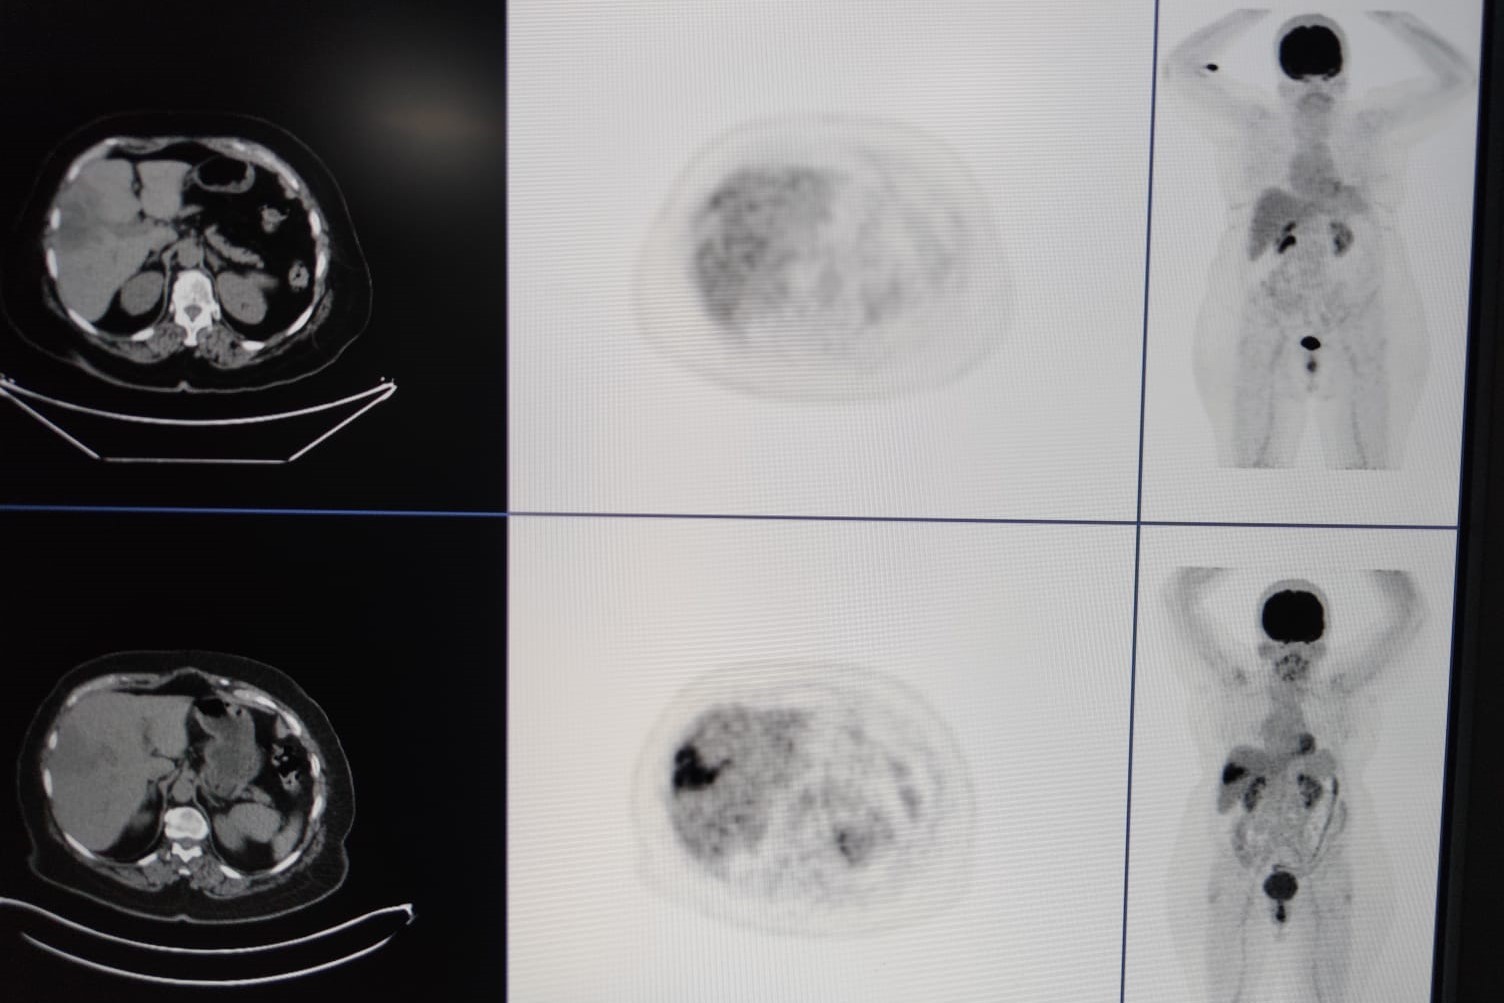

Bir kısmının da tedavisini yapıyoruz. TARE işlemi; belli organlardaki tümör hücrelerine hedef kitleyi besleyen damarın içine girip buna lokal olarak radyoembolizan dediğimiz maddenin enjekte edilmesiyle gerçekleşen bir işlemdir.

Bu işleme yaygın olarak karaciğerin kendi tümörleri ile başka organlardaki tümörün yayılımlarını tedavi ediyoruz” dedi.

Nükleer tıp birimi ile işbirliği içerisinde hastalara tedavi uyguladıklarını ifade eden Şenol, “Bu servisimizde diğer birimlerle işbirliği yaparak çalışıyoruz. Nükleer tıp en fazla işbirliği yaptığımız birimdir. Hastaların çoğu buraya gelmeden nükleer tıp birimine görünüp öyle bize gelir. Hastanın uygunluğu araştırıldıktan sonra öncesinde burada tedavinin bir provası yapılır.

Kitlenin besleyici damarı bulunup buraya bir prova olarak asıl vereceğimiz ilaca benzer bir ilaçla enjeksiyon yapılıyor. Daha sora nükleer tıp biriminde ilacın o kitleyi ne kadar tuttuğu hesaplanıp uygun dozlarda asıl ilaç dozu hesaplanır.